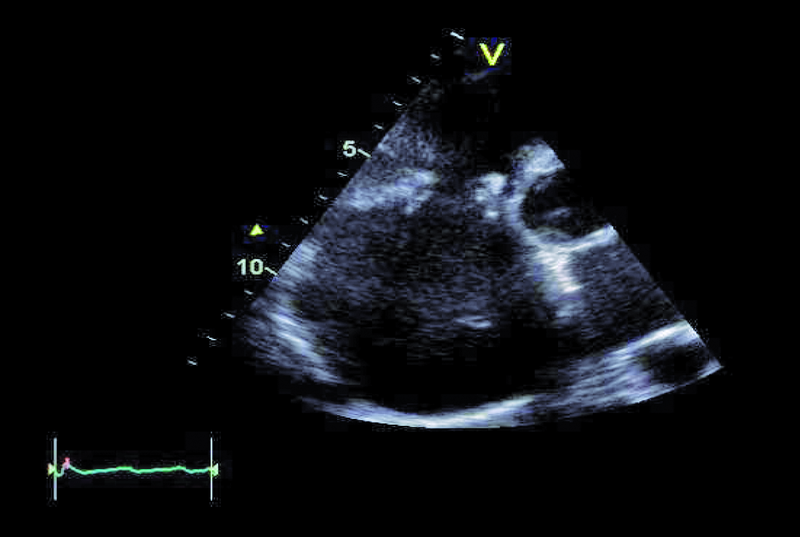

Szczegóły oceny układu krążenia z okresu przeprowadzanych operacji nie były znane. Można było jedynie przypuszczać, że śluzak prawej komory mógł zaburzać funkcję zastawki trójdzielnej, a jego resekcja pozostawiła stopniowo narastającą nieszczelność zastawki. Wymiana zastawki na biologiczną była konieczna, ale spowodowała dalsze problemy u chorego. Degeneracja zastawek biologicznych u osoby młodej może postępować dynamicznie, nawet bez obecności dodatkowych czynników nasilających to zjawisko, jak niewydolność nerek czy nadczynność przytarczyc. Kolejnym czynnikiem, poza wiekiem, wpływającym na odpowiedź immunologiczną, może być samo ujście trójdzielne, w którym procesy wapniowo-fosforanowe w odpowiedzi na rozciąganie płatków są silne. Warto także nadmienić, że zastawki biologiczne stentowe, jak użyta w tym wypadku, charakteryzują się szybszym tempem zwyrodnienia niż zastawki bezstentowe. Rozpoznanie strukturalnego zwyrodnienia bioprotezy w ujściu trójdzielnym nie powinno nastręczać trudności. Wczesnymi objawami procesu jest pogrubienie i usztywnienie płatków, które stają się w obrazie ultradźwiękowym jaśniejsze i nieregularne w zarysie (ryc. 1, 2). Ponieważ proces postępuje, włóknienie i zwapnienia obejmują najpierw spoidła, a następnie całe płatki i pierścień zastawki. W przedstawionym przypadku zwyrodnienie prowadzi zarówno do stenozy, jak i niedomykalności. O stenozie zastawki w ujściu trójdzielnym zawsze należy myśleć, gdy gradient średni napływu przekracza 6 mm Hg (ryc. 3). Niedomykalność trójdzielna uważana jest za istotną, kiedy talia strumienia ma szerokość co najmniej 6 mm (ryc. 4). Warto dodać, że rejestrowane zmiany hemodynamicznie są podobne do tych, jakie obserwuje się w natywnej zastawce trójdzielnej np. w rzadkim uszkodzeniu poreumatycznym. Chory ma wskazania do kolejnej interwencji kardiochirurgicznej i operacja w tym wypadku nie powinna być odkładana, żeby nie doprowadzić do narastającej niewydolności jam prawego serca. By uzupełnić ocenę, zarejestrowano projekcję na drogę odpływu prawej komory (ryc. 5). Wykluczono cechy nadciśnienia płucnego i niedomykalność zastawki płucnej. Zwrócono uwagę na istotnie poszerzone jamę prawego przedsionka i żyłę główną dolną (ryc. 6), odpowiadające nieprawidłowościom w badaniu fizykalnym – hepatomegalii i obrzękom obwodowym. Poza operacją można rozważyć wykonanie zabiegu techniką przezcewnikową i wszczepienie zastawki Edwards SAPIEN lub Melody (valve-in-valve). W tym wypadku na decyzji o leczeniu operacyjnym zaważyły jednak preferencja chorego i doświadczenie ośrodka.